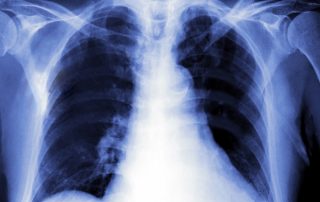

Which types of X-rays & scans have the most radiation?

How much radiation do you get from X-rays & scans? Are X-rays dangerous? And what about other scans? This article is not meant to scare you. Every day medical imaging improves and even saves lives. The imaging tests your doctor requests are usually essential Each time you have an X-ray or [...]